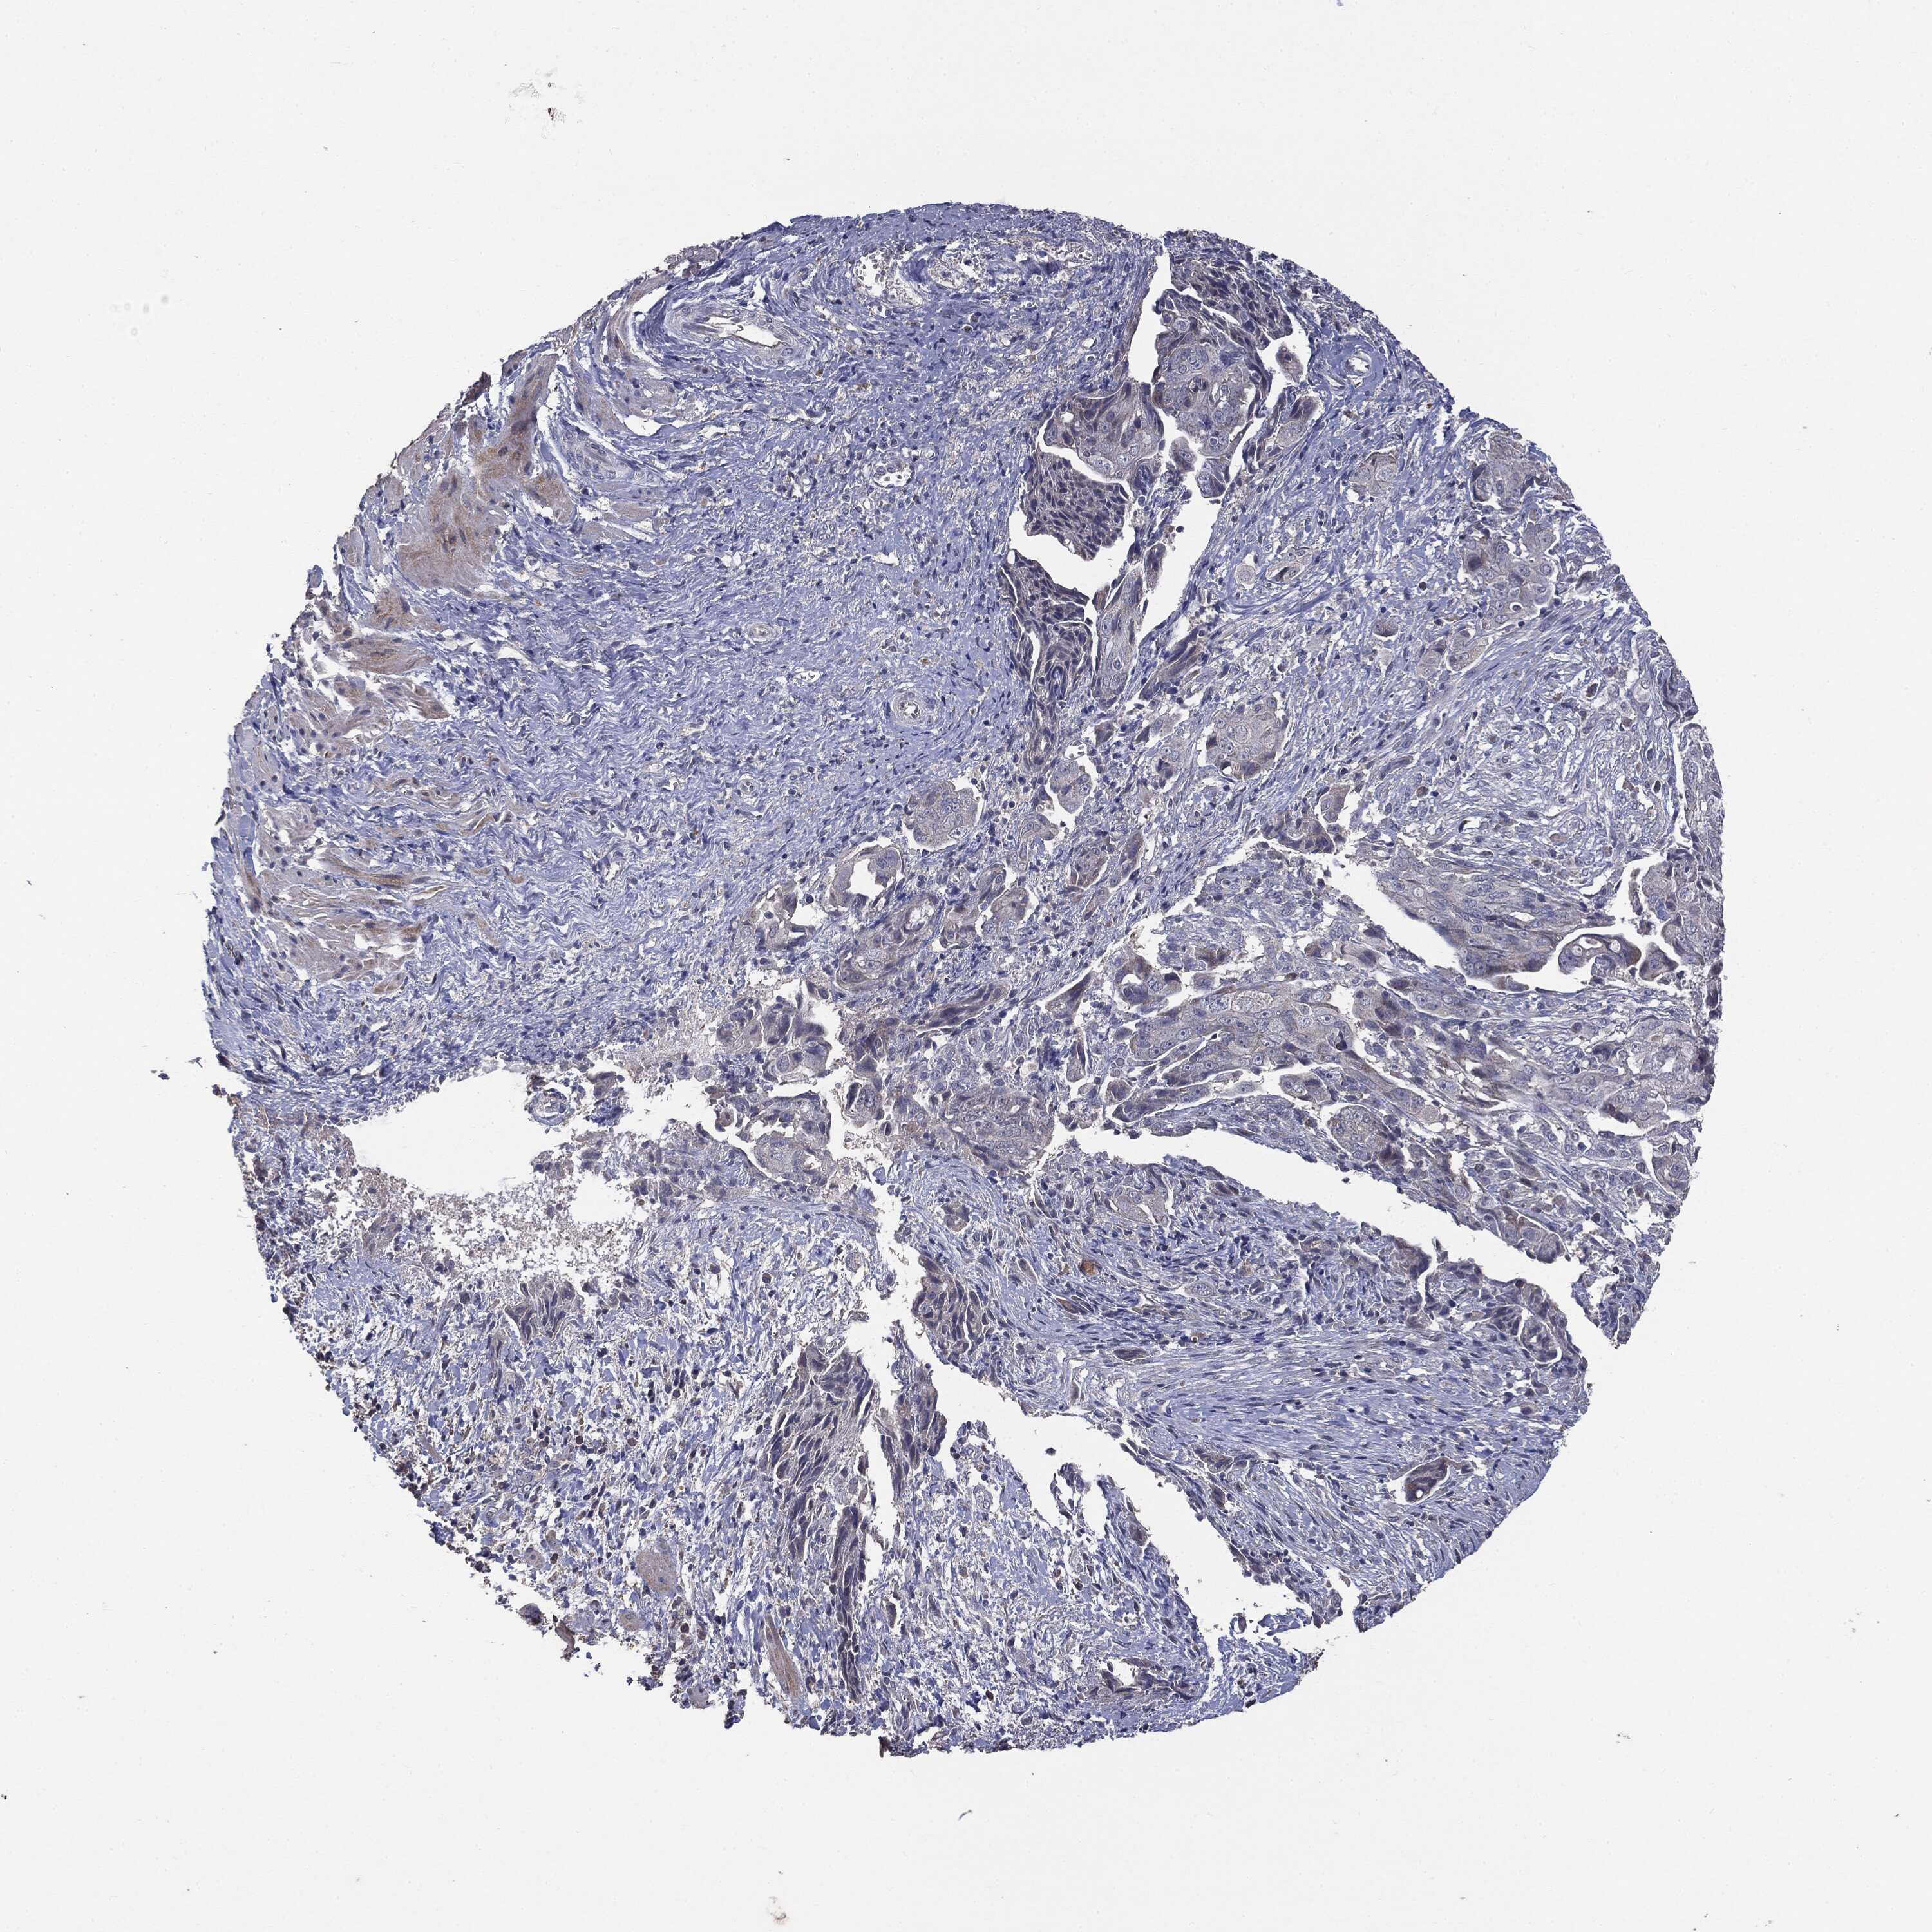

OVARIAN CANCER - Protein expressioni

A mouse-over function shows sample information and annotation data. Click on an image to view it in a full screen mode. Samples can be filtered based on level of antibody staining by selecting one or several of the following categories: high, medium, low and not detected. The assay and annotation is described here.

Note that samples used for immunohistochemistry by the Human Protein Atlas do not correspond to samples in the TCGA dataset.

Antibody stainingi

Antibody staining in the annotated cell types in the current human tissue is reported as not detected, low, medium, or high, based on conventional immunohistochemistry profiling in selected tissues. This score is based on the combination of the staining intensity and fraction of stained cells.

Each image is clickable and will lead to virtual microscopy that enables deeper exploration of all samples and also displays staining intensity scores, fraction scores and subcellular localization as well as patient and tissue information for each sample.

CAB069425

Cystadenocarcinoma, serous, NOS